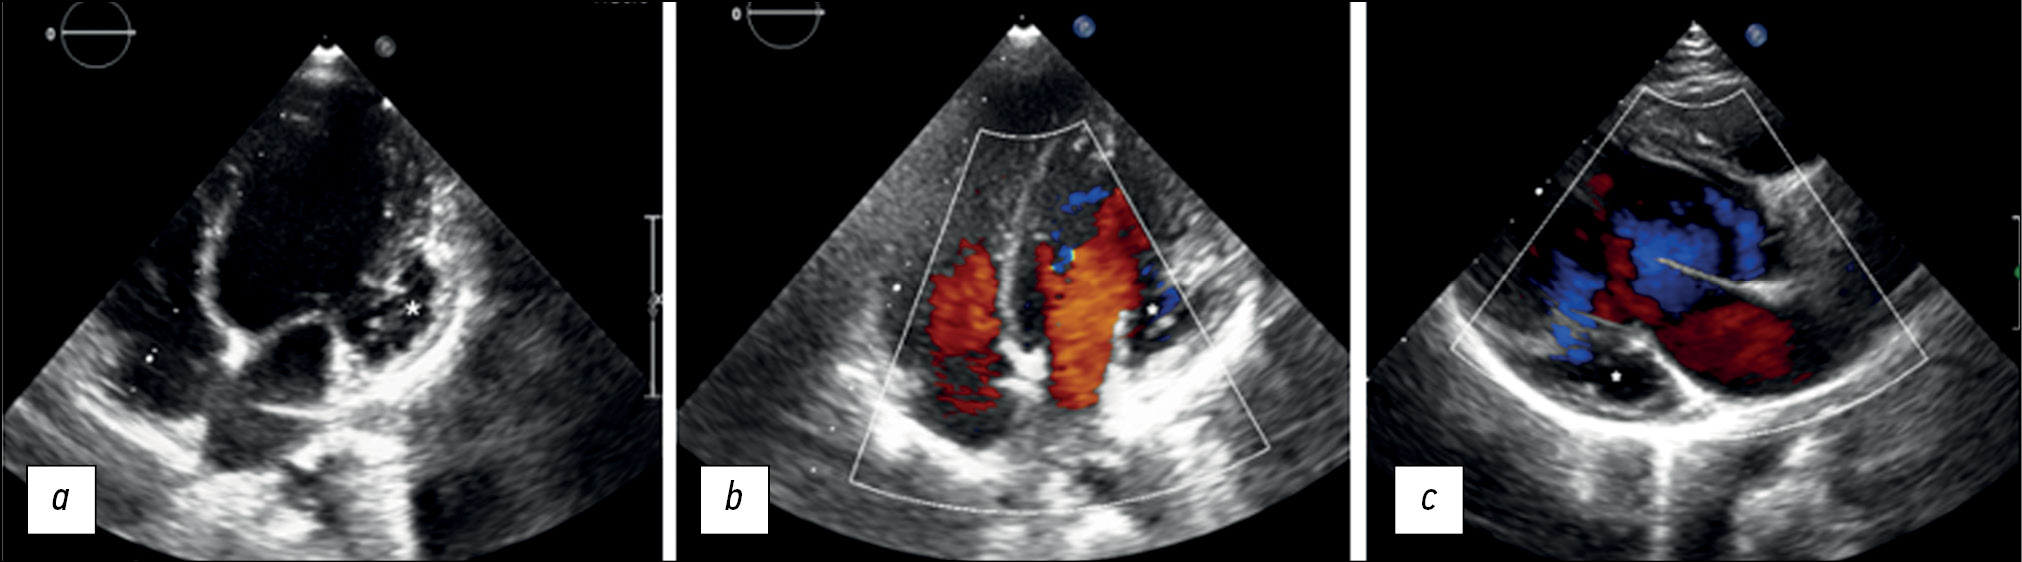

Трудности диагностики миокардита: клинический случай

Миокардит нередко является трудным для диагностики заболеванием сердца. Сложности его диагностики объясняются неспецифической симптоматикой или «стёртой» клинической картиной, отсутствием патогномоничных признаков при физикальном обследовании, а также тем обстоятельством, что эндомиокардиальная биопсия, являющаяся «золотым стандартом» диагностики, — это инвазивная процедура, которая проводится по строгим показаниям ограниченному количеству пациентов. Тем не менее, по мере развития лучевой диагностики у клиницистов появилась возможность неинвазивной диагностики симптомов воспалительного поражения миокарда, в том числе отёка и миокардиального фиброза, с помощью магнитно-резонансной томографии сердца.

В статье представлен клинический случай пациента молодого возраста с симптомами острого коронарного синдрома, у которого при этом не было выявлено признаков поражения коронарных артерий. С учётом повышения активности кардиоспецифических ферментов и уровней маркёров воспаления, выраженных изменений на электрокардиографии с положительной динамикой, а также факта перенесённой накануне инфекции, был заподозрен миокардит. В результате проведения магнитно-резонансной томографии сердца в динамике диагноз был подтверждён. Таким образом, показана роль визуализирующей методики для дифференциальной диагностики ишемического и воспалительного поражения сердца.

Некомпактный миокард и аневризма левого желудочка у 6-летнего ребёнка

Аннотация

Некомпактный миокард — редкий тип кардиомиопатии, часто сопровождающийся аневризмой желудочка. В статье описан клинический случай 6-летней девочки, поступившей в нашу клинику с жалобами на плохое самочувствие при физической нагрузке. Эхокардиография выявила выраженную трабекулярность стенки левого желудочка и выбухание в области базально-боковой стенки, что соотвествует аневризме и некомпактности миокарда левого желудочка. На магнитно-резонансной томографии сердца наличие некомпактности миокарда было подтверждено соотношением некомпактного слоя к компактному 2,6:1. Кроме того, была выявлена систолическая дисфункция и аневризма левого желудочка с рубцеванием миокарда. Коронарная ангиография исключила поражение коронарных артерий, что позволило предположить природу рубцевания эндомиокарда как результат нарушения микроциркуляции в некомпактном слое миокарда.